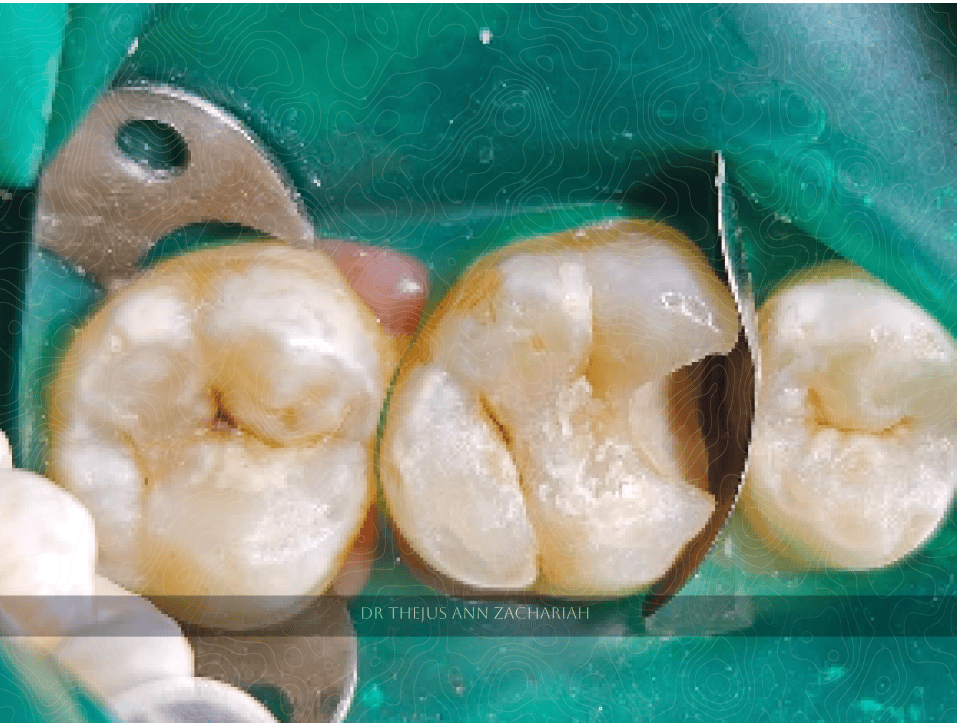

Pre-Operative

alt text

Pin Point Pulp Exposure